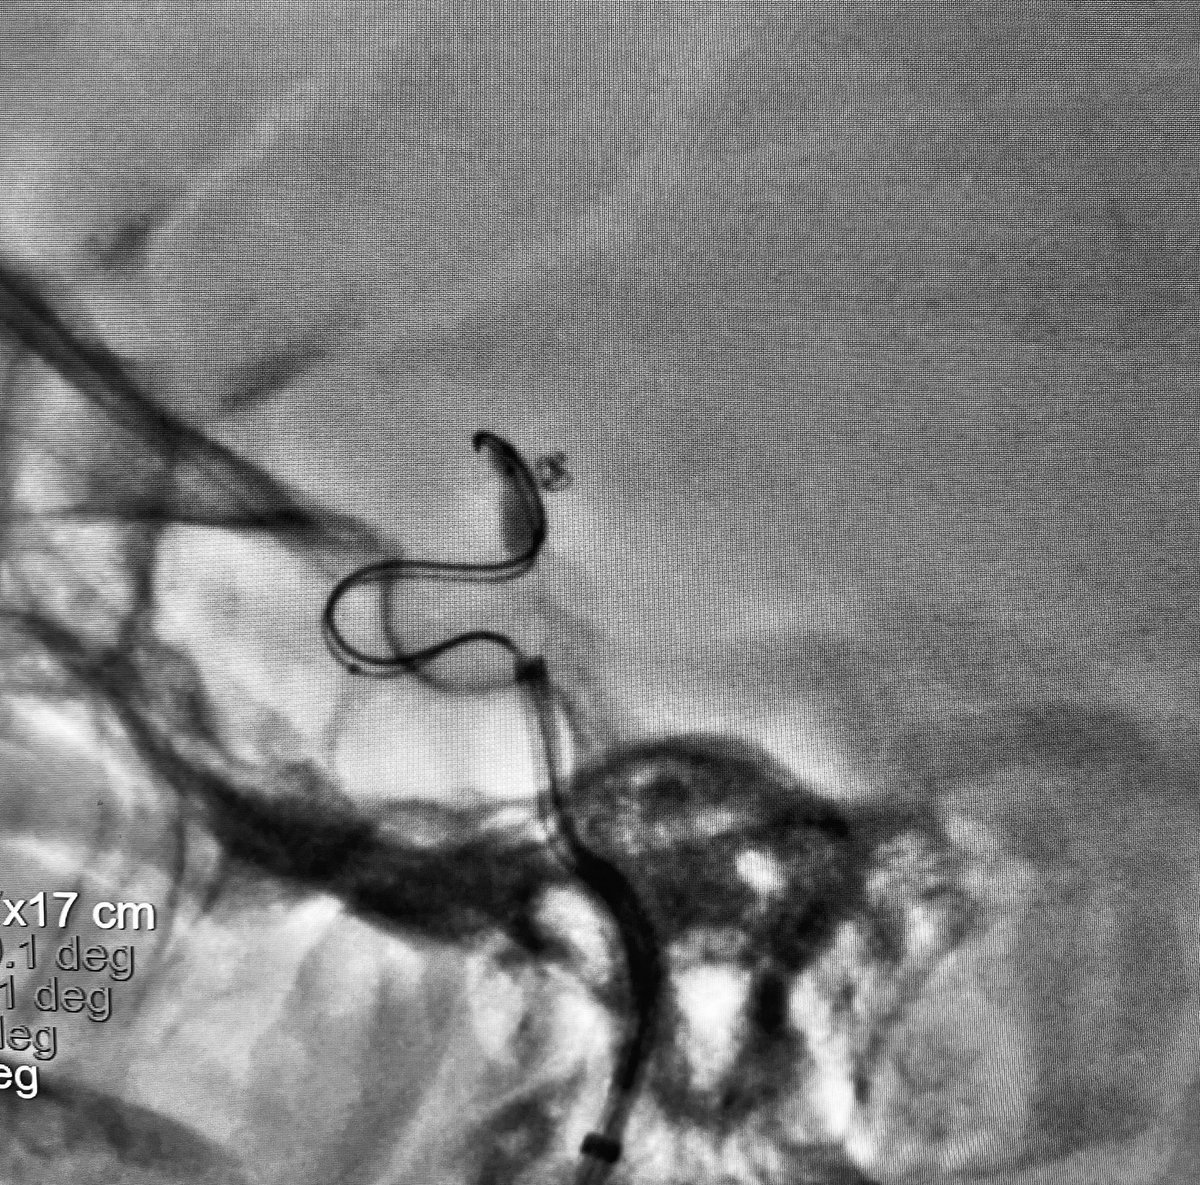

FINAL DECISSION

As suggested by some of the participants:

- Huge difference in vessels diameters (A1 1.5 mm y ICA 3 mm).

- Risk of flow compromise with a cross flow diverter in the MCA.

- Technically challenging to place the flow diverter over the aneurysm and leave the device only on the A1 segment.

We decide to do it across the AcomA, from the left side.

When deploying a flow diverter, we can "easily" decide where to start, but we cannot know exactly where to end.

By crossing the AcomA, we get the same diameter throughout the vessel to be treated, in addition to controlling the stent landing.

English